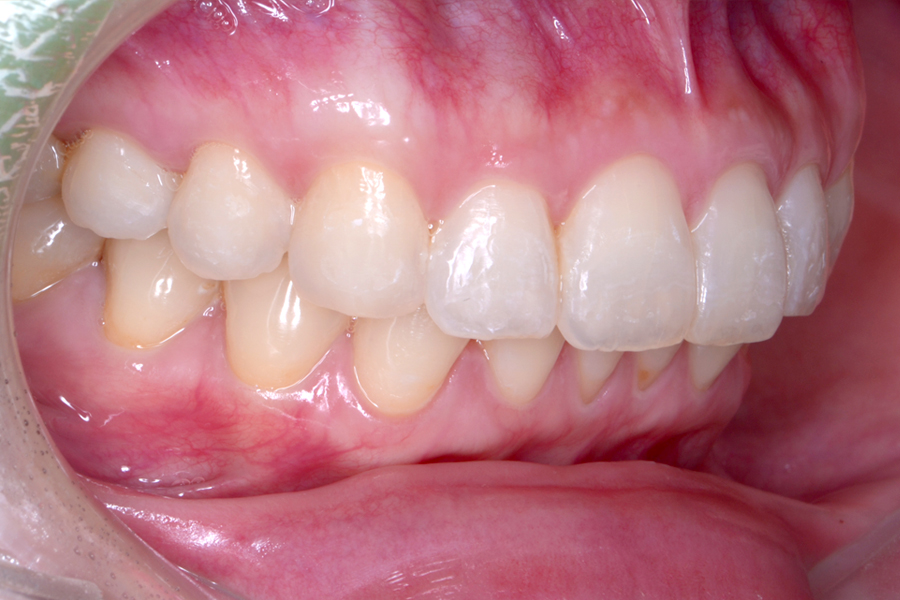

• 治療後